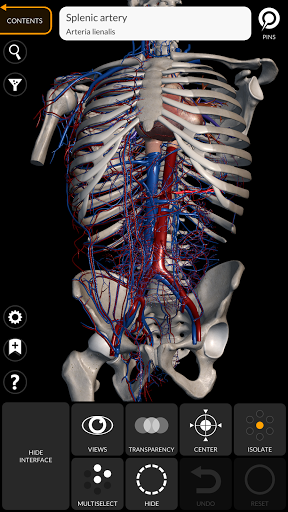

"Anatomy 3D Atlas" дозволяє легко та інтерактивно вивчати анатомію людини.

Завдяки простому та інтуїтивно зрозумілому інтерфейсу можна спостерігати кожну анатомічну структуру під будь-яким кутом.

Анатомічні 3D-моделі особливо деталізовані та мають текстури з роздільною здатністю до 4k.

• Серцево-судинна система

• Можливість приховування або ізоляції однієї чи кількох вибраних моделей

• Функція прозорості

• Вибравши модель або шпильку, з’явиться відповідний анатомічний термін